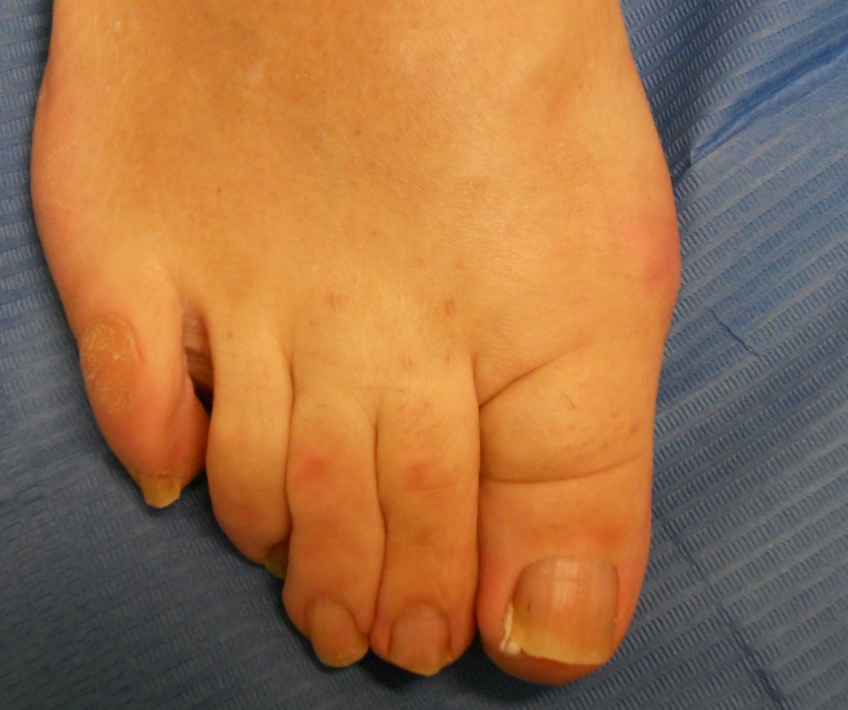

Hallux valgus (juanete) y dedos en garra

Hallux valgus (juanete) y dedos en garra: antes Hallux valgus (juanete) y dedos en garra: después